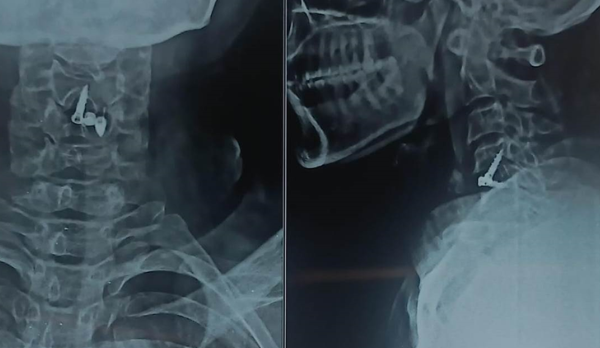

Trustindex verifies that the original source of the review is Google. I visited Dr. Nitish Agarwal for my severe back pain and shoulder issue. He checked my MRI very carefully and gave the perfect diagnosis. Yesterday, he performed the procedure (Root Block and Shoulder Injection), and it was completely painless. He is an expert and targeted the exact nerve point causing the trouble. Very helpful and humble doctor. Highly recommended for anyone with spine problems.Posted onTrustindex verifies that the original source of the review is Google. I was unable to make movement and suffered from right foot drop which is equal to halfway paralysis. Dr. Nitish Agarwal performed very fine microscopic surgery on L3, L4 & L5. After 90 days under his treatment I could go for a walk min. 6 kms a day, I have started my regular activities after 120 days. Thank you so much Dr. Nitish Agarwal sir.Posted onTrustindex verifies that the original source of the review is Google. I was suffering from severe back pain, and Dr. Nitish Agrawal has been extremely supportive throughout my treatment. He listened carefully, explained everything clearly, and guided me very well. His treatment has really helped me recover. He is one of the best spine specialists — highly recommended!Posted onTrustindex verifies that the original source of the review is Google. I had consulted many doctors before Dr Nitish for my mother's spine issue,most recommended complex procedures and surgeries. Fortunately we found Dr Nitish and it has been life changing for my mother,she was in immense pain before the simple surgery he did. It's rare to find a surgeon who explains everything in detail and provides such exceptional care even after the surgery. I Would highly recommend him.Posted onTrustindex verifies that the original source of the review is Google. My mother had sustained a fracture to her right hand wrist and we were worried about her recovery due to age factor. One of our family Doctor referred us to Dr. Nitish Agrawal and we visited Dr. Nitish Sir. Dr. Nitish sir ensured that my mother don't need a surgery and treated her by application of plaster (temporary and then cast-iron or Firm plaster) with certain orthopaedic treatment to hand and prescribed oral medication for ensuring recovery is faster without any surgery. Attaching the photo of xray which shows recovery of wrist bone which has rejoined and we are still continuing treatment to ensure my mother is fully recovered and is fit. Thank you Dr.Nitish Agrawal for your support.Posted onTrustindex verifies that the original source of the review is Google. Hi everyone, myself Samadhan. I was suffering from severe spine pain for a long time, and one of my friends suggested I visit Dr. Nitish Agarwal. Honestly, that was the best advice! Dr. Nitish listened to my problem very patiently, explained the cause in detail, and gave me the right treatment. I started feeling better within a short time. He is very polite, knowledgeable, and truly cares for his patients. I highly recommend Dr. Nitish Agarwal for anyone dealing with spine or back pain. Thank you, doctor, for your excellent treatment and support!Posted onTrustindex verifies that the original source of the review is Google. Dr. Nitish Agrawal is an excellent spine specialist who patiently listens, explains the problem clearly, and provides the best treatment options.Posted onTrustindex verifies that the original source of the review is Google. Dr.Nitish sir is an incredible surgeon. I had excellent results from my recent spine surgery. The entire process, from consultation to recovery, was handled with professionalism and care. The outcome has been life-changing. I highly recommend Dr.Nitish agarwal to anyone in need of a spine surgeon.Posted onTrustindex verifies that the original source of the review is Google. A few months back I took treatment for my back pain from dr. Agarwal sir ...last 7-8 years i was suffering with low back pain,unbale to stand for more than 10 minutes..My low back hurts continuously, and also left leg pain was unbearable....i try every possible way of treatment from various suggestion...After several treatment...one of my relative suggested dr. Nitish Agarwal sirs name then I visited Dr. Nitish Agarwal sir in clinic. He suggested me x ray and MRI. On that basis he advise me caudal Block with root block with facet block for pain management. After block my pain goes with in a week. He advise me regular Physiotherapy at home. Now after regular exercise I am pain Free. Dr. Nitish Agarwal is a good doctor for any spine related problem.... Thank u dr. Agarwal Sir 🙏Posted onTrustindex verifies that the original source of the review is Google. My wife had major infection in neck and lower back. She was bedridden. her legs and hands were weak. Then we admit her under Dr. Nitish Agarwal sir and did MRI. He explained that she is having major infection in cervical and lumbar spine. Due to infection her spinal cord is compressed so she was not able to walk. Then sir did operation for neck and removed infected tissue and spinal cord is freed and put a plate. Her lower back is treated with medicine only. She was given 2 months antibiotics by saline and 5 months oral antibiotics were given. He also advised regular exercise. After 15 days of surgery she started walking with support. Now after 1 year she is completely alright and walking like a normal person. She is regularly doing all her activities. Now she can also travel by 2 wheeler. Thank you to Dr. Nitish Agarwal sir for his expert work in spine. I recommend Dr. Nitish Agarwal for any spine related problem.